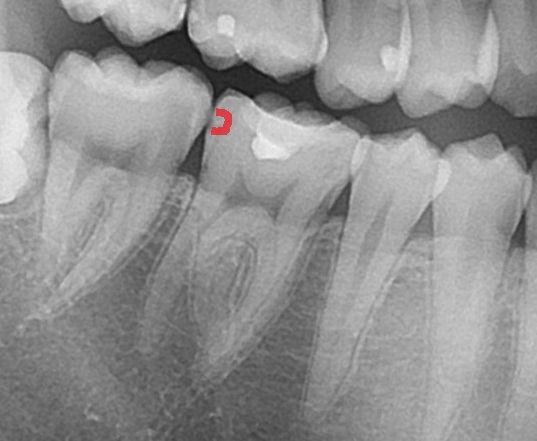

虫歯がある場所は、

赤く示した場所です。歯と歯の間で黒く虫歯の影が確認できました。歯と歯の間の虫歯は自分で気づくことができず進行していきます。レントゲン写真で歯の中の状態が確認できると、虫歯を見つけることができます。